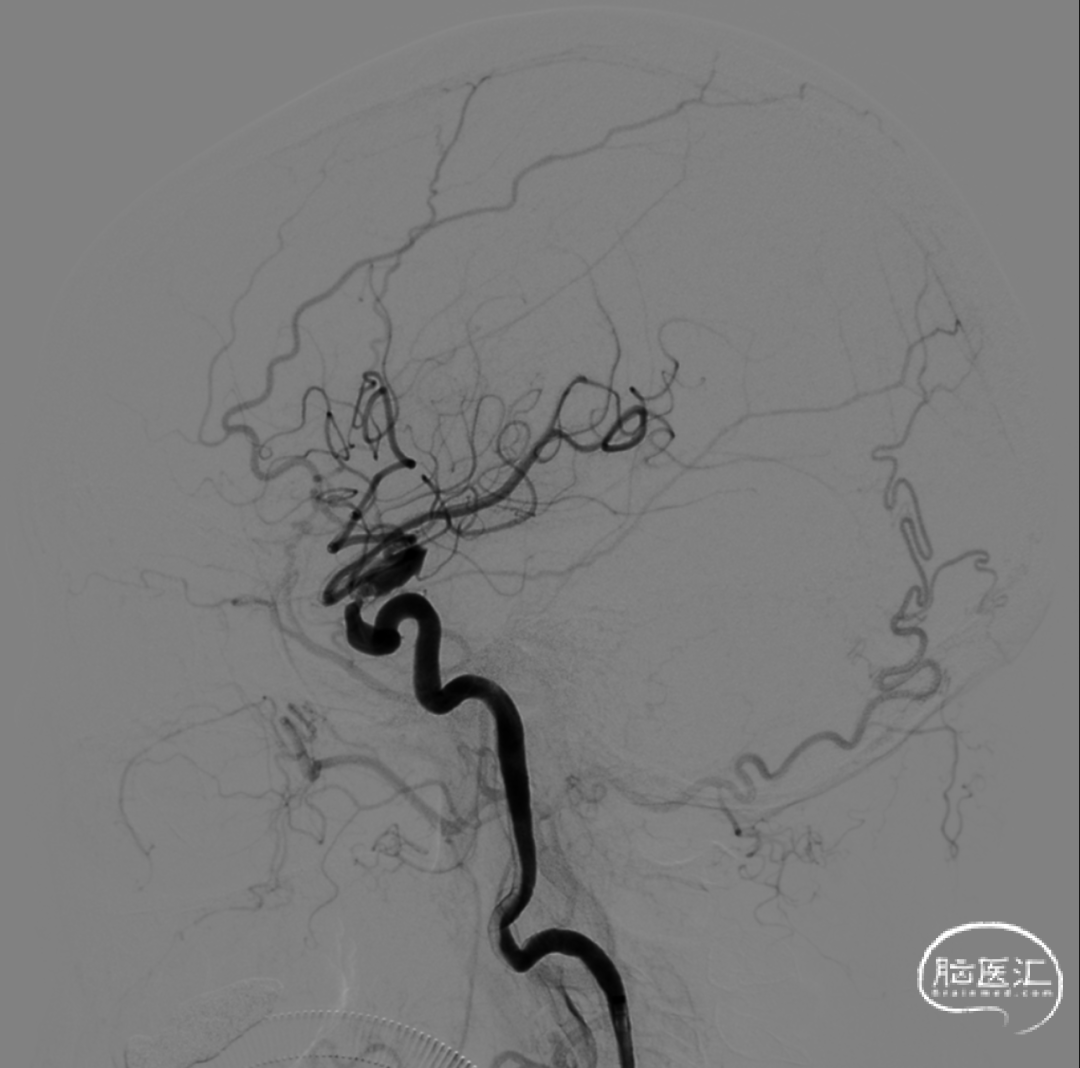

多角度造影明确左侧颈内动脉眼动脉段重度狭窄。

侧位造影